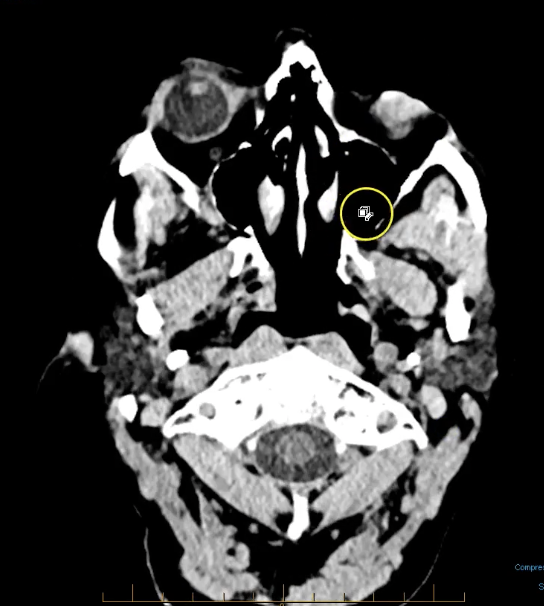

term image

pineal gland- hyperdense. part of endocrine system. secrenes melatonin